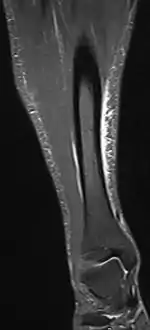

Other potential causes include stress fractures, compartment syndrome, nerve entrapment, and popliteal artery entrapment syndrome.[17] If the cause is unclear, medical imaging such as a bone scan or magnetic resonance imaging (MRI) may be performed.[3] Bone scans and MRI can differentiate between stress fractures and shin splints.[11]